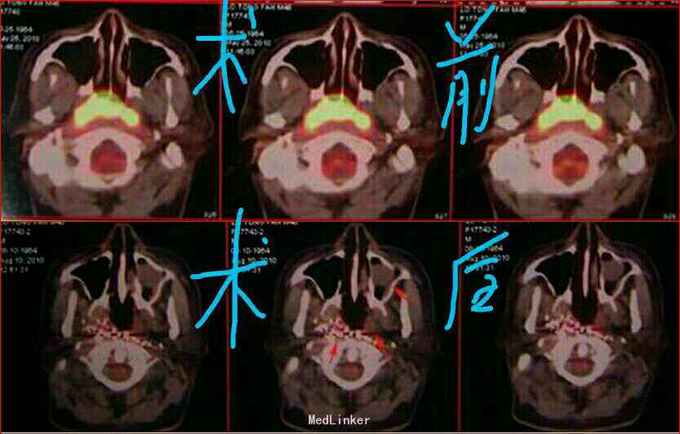

诊断:鼻咽癌放疗后复发并颈部淋巴结转移 治疗方法: 1、5.28日经皮双侧颈外动脉药物灌注术+弹簧圈栓塞术,术前3小时静脉输注泰素150mg,术中灌注顺铂80mg、力朴素90mg,经供血动脉主干分别置入3mmX3mm微钢圈各一个;术后第二天静脉输注顺铂30mg。 2、06.05日CT引导下经皮鼻咽部肿物及颈部淋巴结碘125粒子植入术,术中共用粒子90粒,活度0.8mCi。

2010.08.10复查PET—CT:原鼻咽部肿物及肿大淋巴结明显缩小,活性完全受抑,鼻咽腔扩大,症状消失。